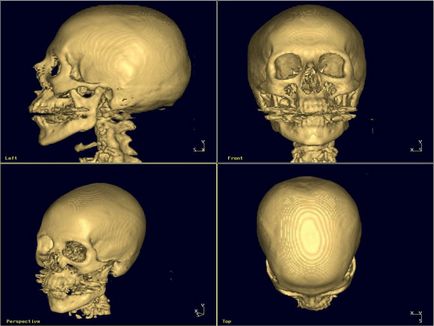

Ce poate fi investigat de cap CT?

Deoarece echipamentul modern, vă permite să obțineți o imagine corectă a structurii interne a osului craniului la cele mai mici detalii (și țesutului moale, se consideră oportun să se utilizeze CT precum RMN în studiul acestor domenii:

- maxilarului (superior și inferior) dentitie;

- osul frontal;

- si a tesutului osos cartilajului a nasului și a pometi;

- țesutul muscular al capului și a coloanei cervicale;

- orice departament al creierului;

- sinusurile paranazale;

- navele, ganglionii limfatici, etc.

Ce poate fi investigat de cap CT